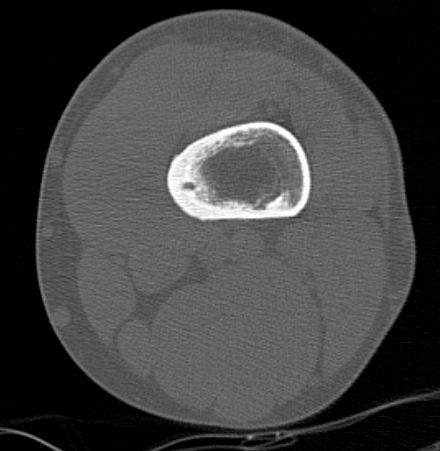

CT

Best investigation

- lucent nidus surrounded by dense bone

Osteoid osteoma tibia